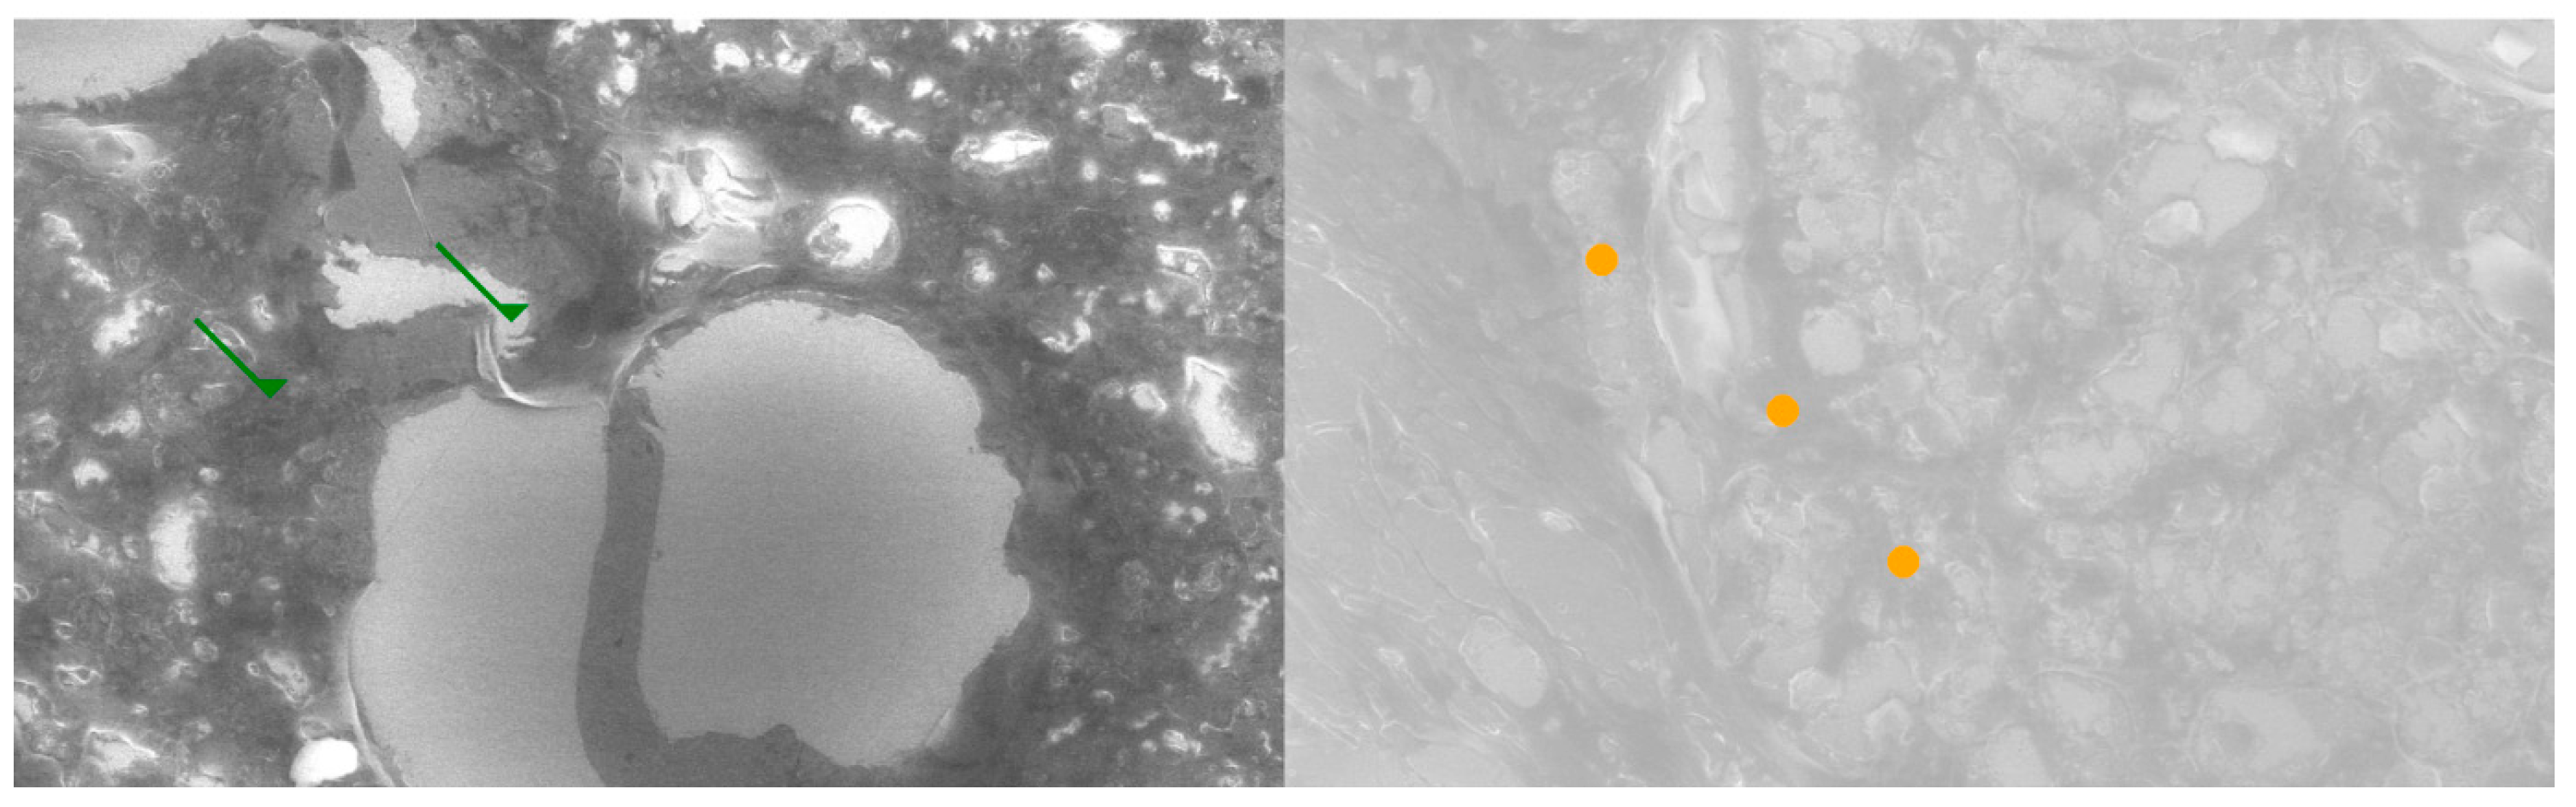

2.3. Results of the SEM Study

Comparative SEM examination at ×1000 magnification revealed striking morphological parallels between thymus and parathyroid tissue. In thymic samples, the stromal scaffold was traversed by fine vascular grooves and channels, consistent with the capillary meshwork required for thymocyte maturation. Although less prominent, parathyroid sections displayed surface depressions and intercellular clefts suggestive of similar microvascular pathways, indicating that both glands may share comparable patterns of vascular organization. At the stromal level, the thymus exhibited a reticular epithelial network with interlacing bridges forming a three-dimensional scaffold, while the parathyroid presented clusters of chief cells with distinct membrane contours and discrete intercellular connections.

Certain parathyroid areas even displayed reticular-like meshes, reminiscent of the thymic scaffold and suggestive of structural convergence. In addition, concentric epithelial whorls typical of Hassall’s corpuscles were readily identified in thymic tissue, whereas the parathyroid revealed focal stromal nodules with partially lamellar arrangements, not identical but evocative of concentric condensations and consistent with the possibility of shared embryonic remnants.

Further similarities were observed at the level of cell surface specialization. Thymic epithelial cells exhibited microprojections and membrane folds that expanded the contact surface for intercellular communication, while parathyroid chief cells displayed less dense but clearly identifiable microvillous projections. Such surface domains provide morphological support for the immunohistochemically demonstrated localization of receptors, including Thymosin and PTH1R.

Age-related differences were also noted: the thymic architecture appeared relatively preserved, with dense stromal and cellular organization, whereas the parathyroid showed mature chief cell fields with limited fibrous encapsulation, yet still retained organizational echoes of the thymic pattern. These ultrastructural observations highlight shared microvascular reliefs, convergent stromal frameworks, analogies to Hassall’s corpuscles, and comparable microvillous surface domains. Collectively, they reinforce the hypothesis that the thymus and parathyroid are not merely embryological neighbors but functionally interconnected glands, potentially linked through a parathyroid–thymus possible portal system (Figure 5 and Figure 6).

Figure 5. Comparative SEM analysis of thymus (left) and parathyroid (right) at ×1000 magnification. In the left panel green arrows highlight vascular-like networks suggestive of fine microcirculatory patterns. In the right panel, orange bullets indicate stromal cell arrangements and extracellular matrix similarities compared to the thymic reticular scaffold. These ultrastructural analogies support the hypothesis of shared vascular and stromal organization across the two glands.